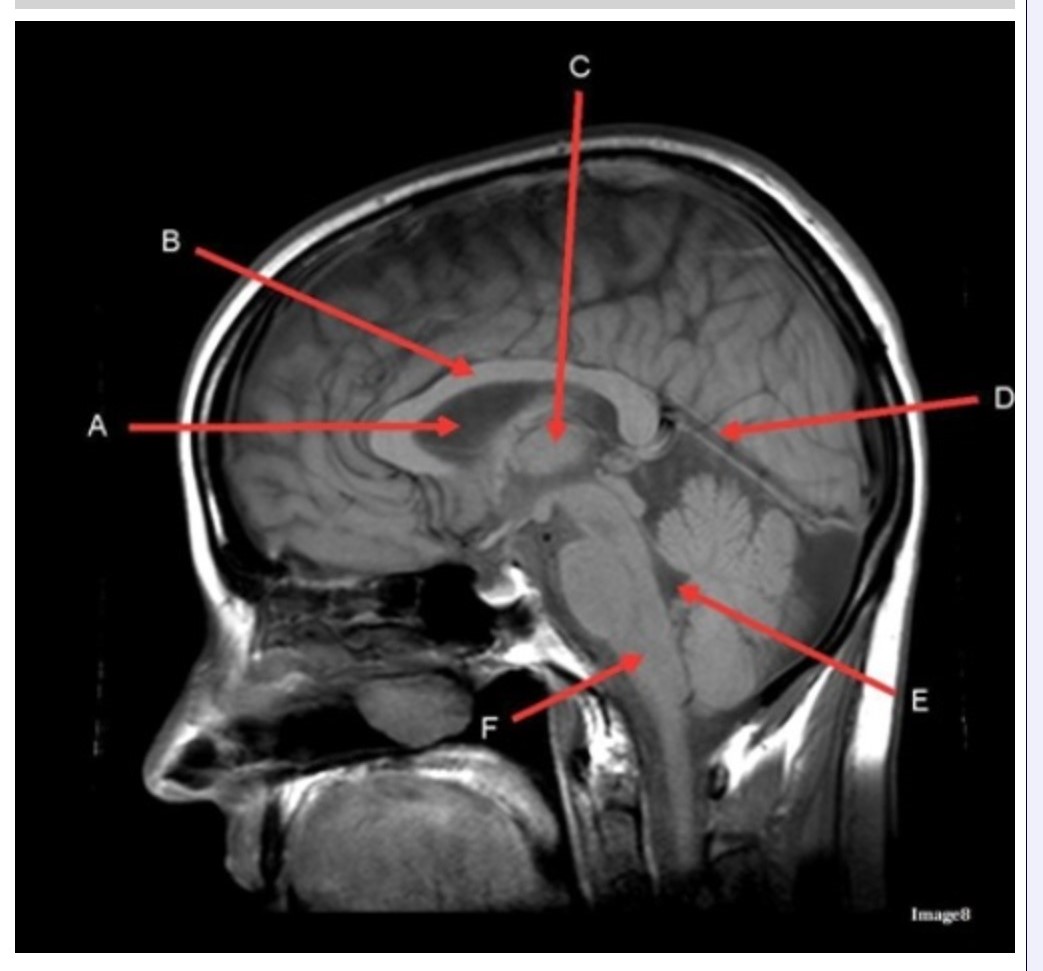

Letter C in Image 8 is pointing to:

A. Tentorium

B. Corpus callosum

C. Thalamus

D. Fourth ventricle

E. Medulla oblongata

Letter F in Image 8 is pointing to:

A. Tentorium

B. Cerebellum

C. Thalamus

D. Fourth ventricle

E. Medulla oblongata

Letter A in Image 8 is pointing to:

A. Tentorium

B. Corpus callosum

C. Hypothalamus

D. Fourth ventricle

E. Lateral Ventricle

Letter E in Image 8 is pointing to:

A. Tentorium

B. Cerebellum

C. Thalamus

D. Fourth ventricle

E. Medulla oblongata

Letter B in Image 8 is pointing to:

A. Tentorium

B. Corpus callosum

C. Hypothalamus

D. Fourth ventricle

E. Medulla oblongata

Letter D in Image 8 is pointing to:

A. Tentorium

B. Cerebellum

C. Thalamus

D. Fourth ventricle

E. Medulla oblongata

Image 8 is an example of a _______ weighted sequence acquired in the _______ scan plane.

A. T1; Axial

B. T1; Sagittal

C. T2; Axial

D. T2; Sagittal